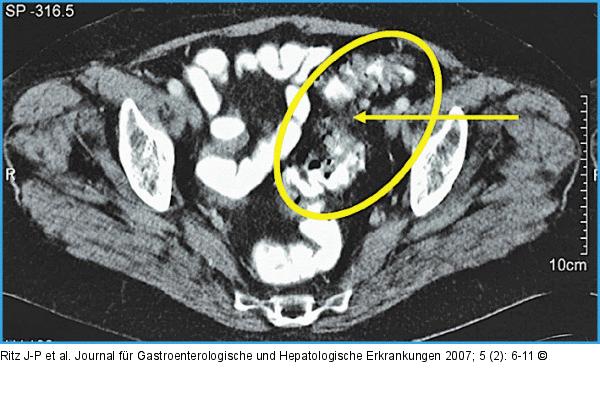

Abbildung 9: Chronische Sigmadivertikulitis mit Wandverdickung Chronische Sigmadivertikulitis mit Wandverdickung und postentzündlicher Stenose (mit Pfeil markiert) im Stadium HS III |

Chronische Sigmadivertikulitis mit Wandverdickung und postentzündlicher Stenose (mit Pfeil markiert) im Stadium HS III |